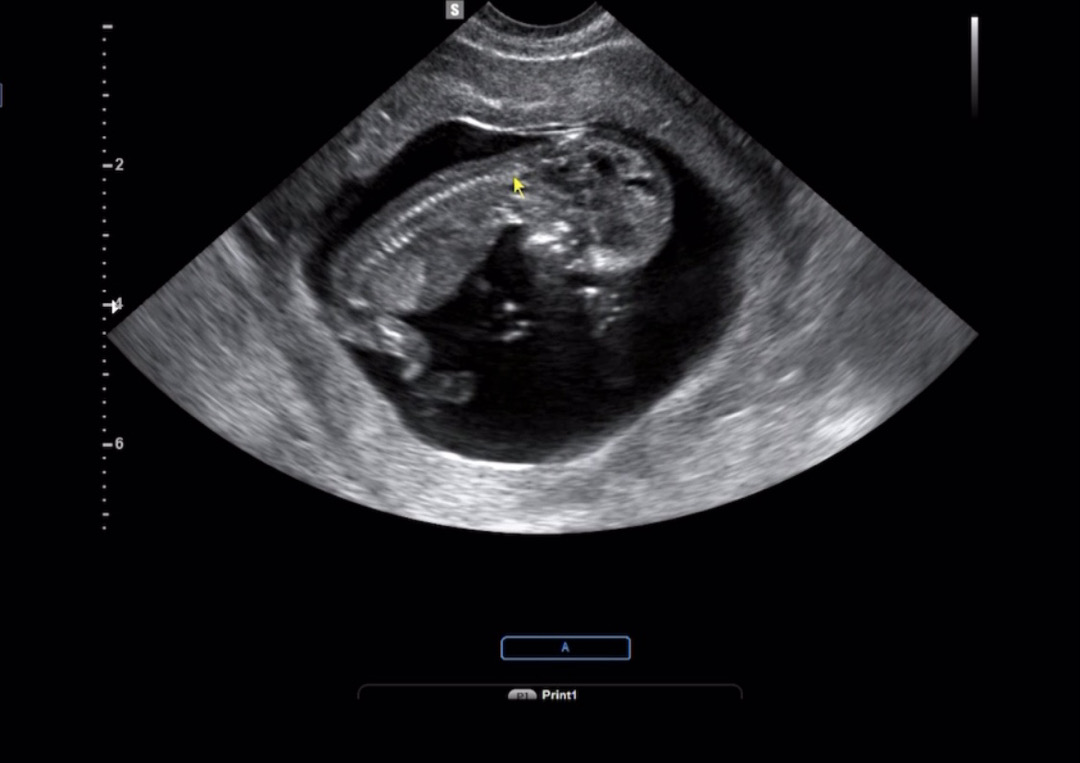

성별보러갔는데 이자세일줄 ㅠㅋ

이 사진으론 못보겠죠...?

엎드려두 돌기가 보이면 확인될텐데 ㅠ 저도 저렇게 아기가 다리를 올리고있어서 가려져있더라구요!!